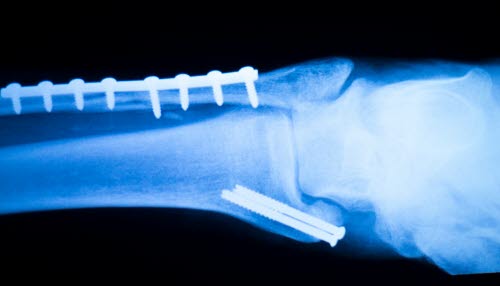

Fibulabrudd med større forskyvninger (se røntgenbilde), brudd i begge ankelkulene (bimalleolære brudd) der minst en av dem er forskjøvet, revner i syndesmosen, høye fibulabrudd (hvis det ikke skyldes direkte slag) - er alle bruddtyper som krever operasjon.

Om mulig forsøker man å operere innen 6-8 timer. Dersom det har gått for lang tid og hevelsen er for stor, settes bruddet på plass og man anlegger en gipsstøtte. Operasjonen utsettes da til hevelsen har gått ned, som regel etter 4-6 dager. Brudd i den utvendige (laterale) malleolen festes med skrue eller støtteplate. Brudd i den innvendige (mediale) malleolen festes med skrue(r), pinner eller ståltråd (cerclage). Avrevet syndesmose festes med skrue som settes fra fibula inn i tibia.